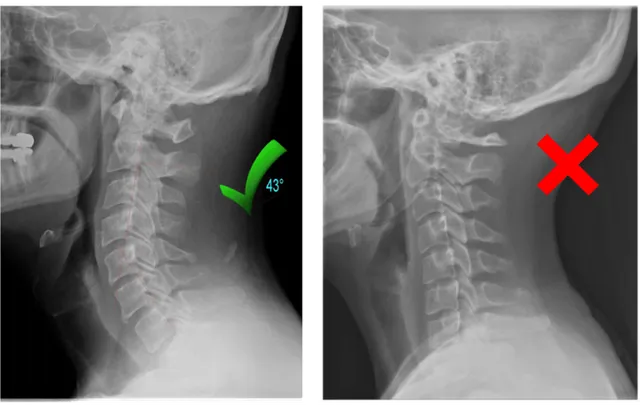

2. Nacken har tappat sin naturliga position

År av mobilanvändning, datorarbete och dåliga sovpositioner kan göra att nackens naturliga kurva förändras.

När det händer kan vissa delar av nacken få ta mer belastning än de är byggda för.